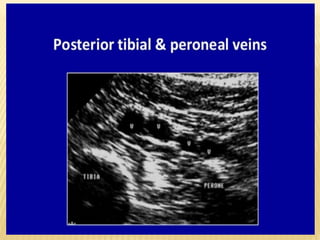

VEINS OF LOWERLIMB Greater Saphenous Vein Small Saphenous Vein Femoral Vein Profunda Femoris Vein Popliteal Vein Peroneal Vein Anterior & Posterior Tibial Vein